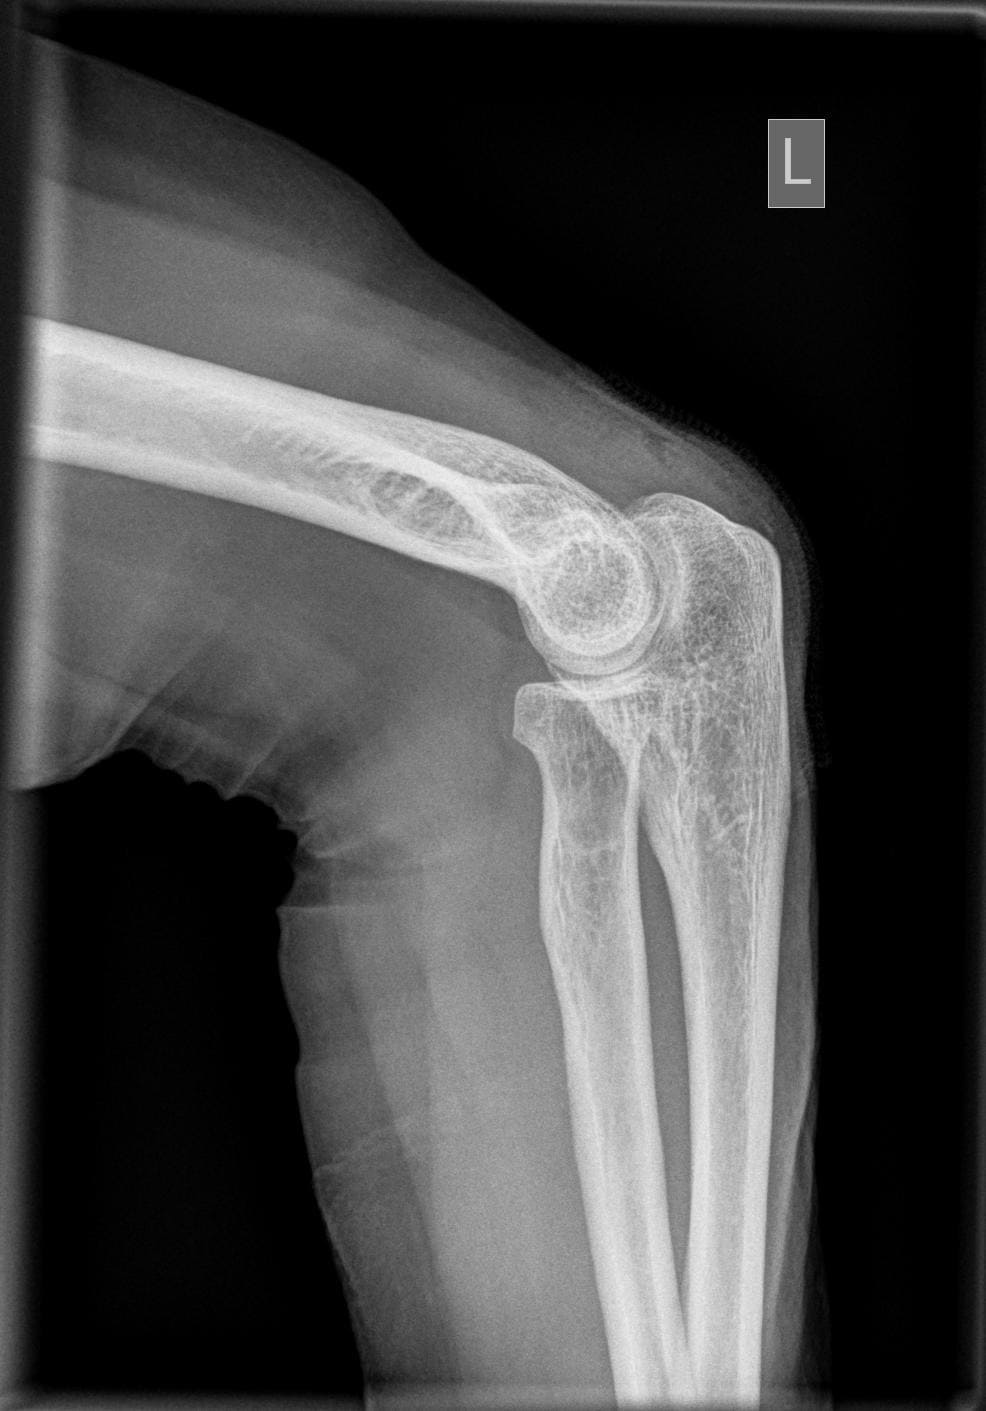

Ellenbogen seitlich

Ellenbogenseit.jpg

Fehler

Der distale Oberarmteil ist schräg projiziert, d.h. die beiden Gelenkrollen überdecken sich nicht, sondern erscheinen über- resp. untereinander. Ursache hier ist die Schrägprojektion bei hängendem Oberarm.

Abhilfe

Es müssen Oberarm und Unterarm auf Schulterhöhe waagerecht aufliegend.